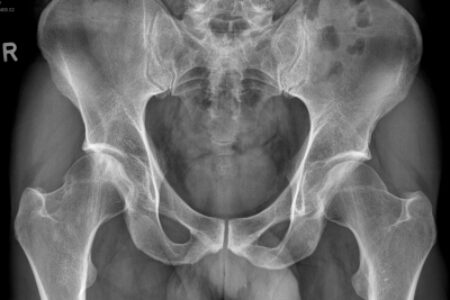

Heupnecrose: MRI & Röntgen